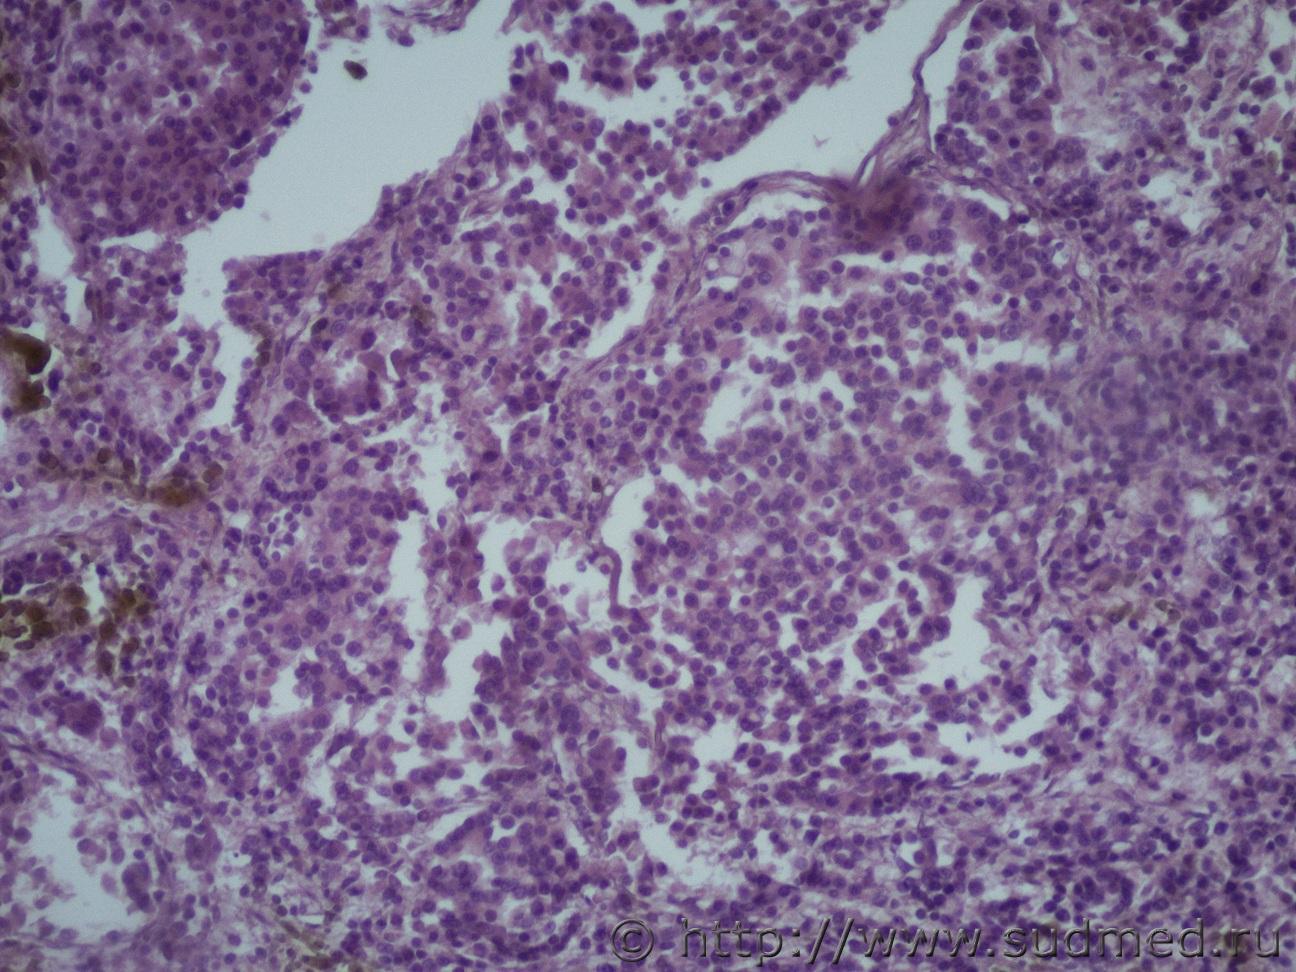

Ув. коллеги помогите определиться с раком. Муж 60 лет. Новообразование предстательной железы с метастазами в легкие, печень, диафрагмуСудебная медицина - Прикрепленное изображение Судебная медицина - Прикрепленное изображениеСудебная медицина - Прикрепленное изображениеСудебная медицина - Прикрепленное изображениеСудебная медицина - Прикрепленное изображение

Поставил бы криброзную ад-карциному.

В данном случае можно поставить аденокарциному. Если на первых фото ткань простаты, то можно сказать, что опухоль с высоким индексом Глисона, видны солидные пласты опухолевых клеток, хотя кое-где все же прослеживаются железистые структуры. Более прицельные снимки бы глянуть, на большем увеличении.

Ацинарная аденокарцинома.

криброзную

Есть и эти структуры.

Да первые это простата. Вот еще снимки